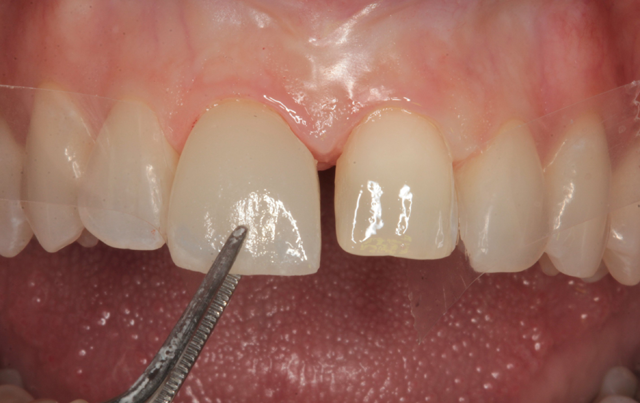

The veneers were delivered to the teeth using a cotton plier (Fig. 17). A placement instrument (Veneer Stabilizer, Hu-Friedy) was used to lightly seat the veneers (Fig. 18). Excess resin cement at the margins was removed with a brush (Fig.19).

Fig. 16 Fig. 17 Fig. 18